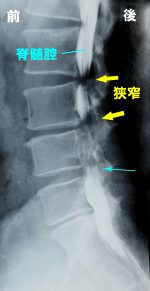

神経の通り道(脊髄腔や神経根)、椎間板などはレ

ントゲンに写りません。ここにレントゲンに写る液(造

影剤)を注入してレントゲンやCTをとるのが造影検査

です。左側の写真で、水色の矢印の部分から造影剤

を注入しています(ミエログラフィー)。側面像(左側)

では、造影された脊髄腔が2か所ほどくびれており、

そこで脊柱管が狭くなっていることがわかります。正

面像(右側)では、神経根が造影されている部分と、

造影されずに不明瞭になっている部分があります。